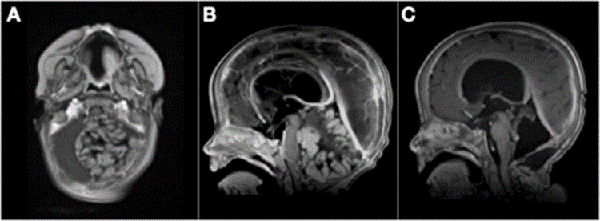

Figura 2: A) Paciente de 3 meses de vida, sexo masculino, consultó por macrocefalia e irritabilidad, IRM de cerebro con contraste EV donde se evidenció lesión intraventricular izquierda con extenso edema cerebral ipsilateral. Se realizó cirugía con exéresis parcial debido a labilidad hemodinámica. Anatomía patológica informó papiloma de plexos coroideos. B) IRM de cerebro 1 mes postquirúrgica. Se decidió diferir la re-exploración. C) Se realizó nueva cirugía luego de 6 meses. IRM de cerebro 1 mes post quirúrgica donde se constató la exéresis completa. Paciente evolucionó favorablemente, recuperó pautas madurativas pérdidas.